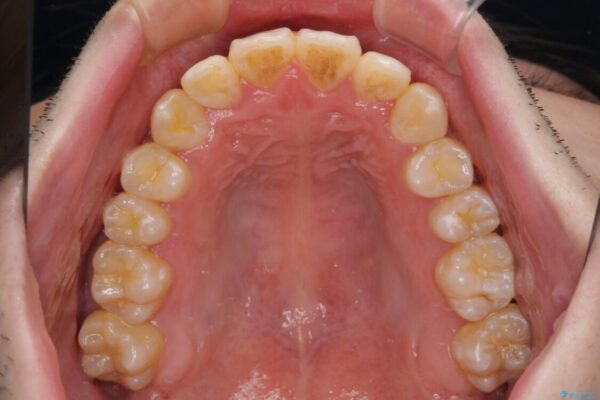

八重歯や奥歯の噛みにくさを気にして来院された患者様です。

前歯のクロスバイトや八重歯の他に、左右最後臼歯のシザーズバイト(鋏状咬合)が認められました。

治療前

• 全顎的なクロスバイト 補助装置を用いてワイヤー矯正 治療前画像